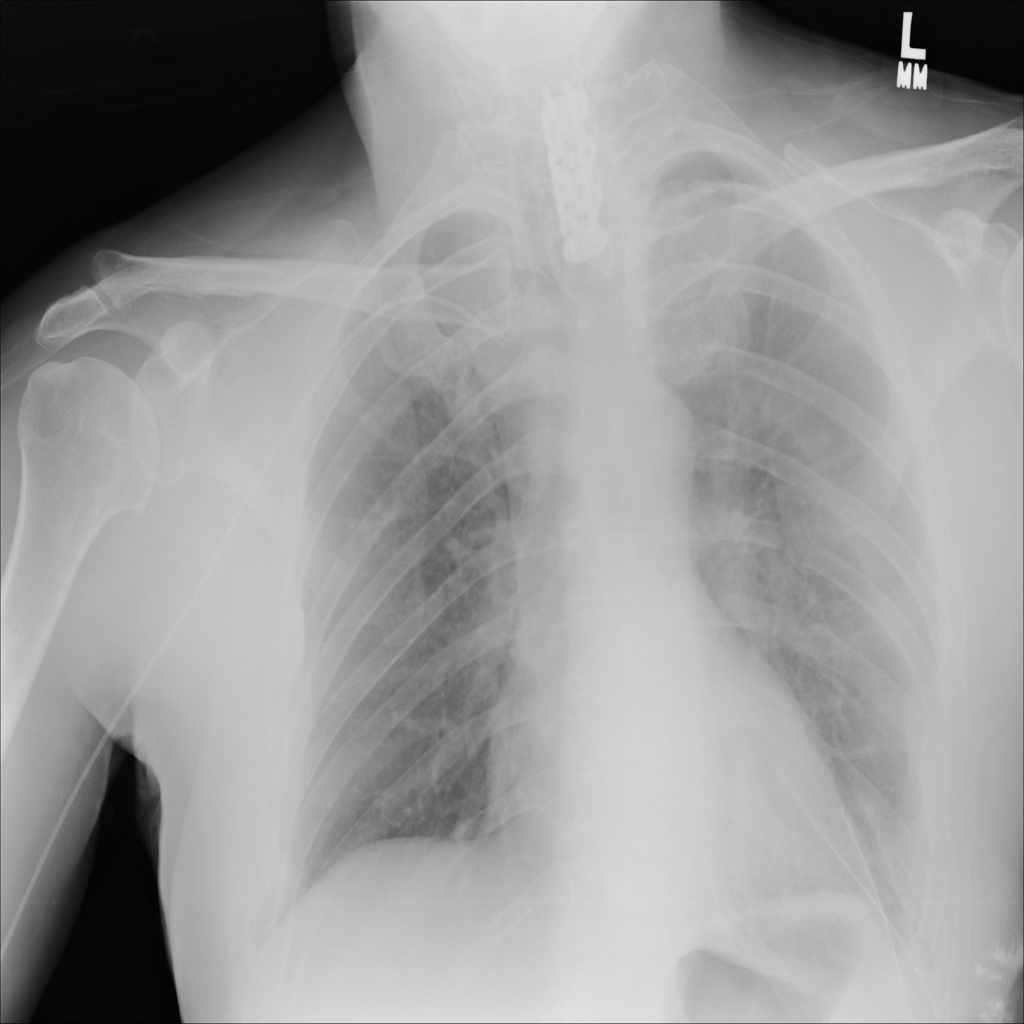

PAT-DC57 · IMG-000Consolidation

PAT-DC57 · IMG-000

AP